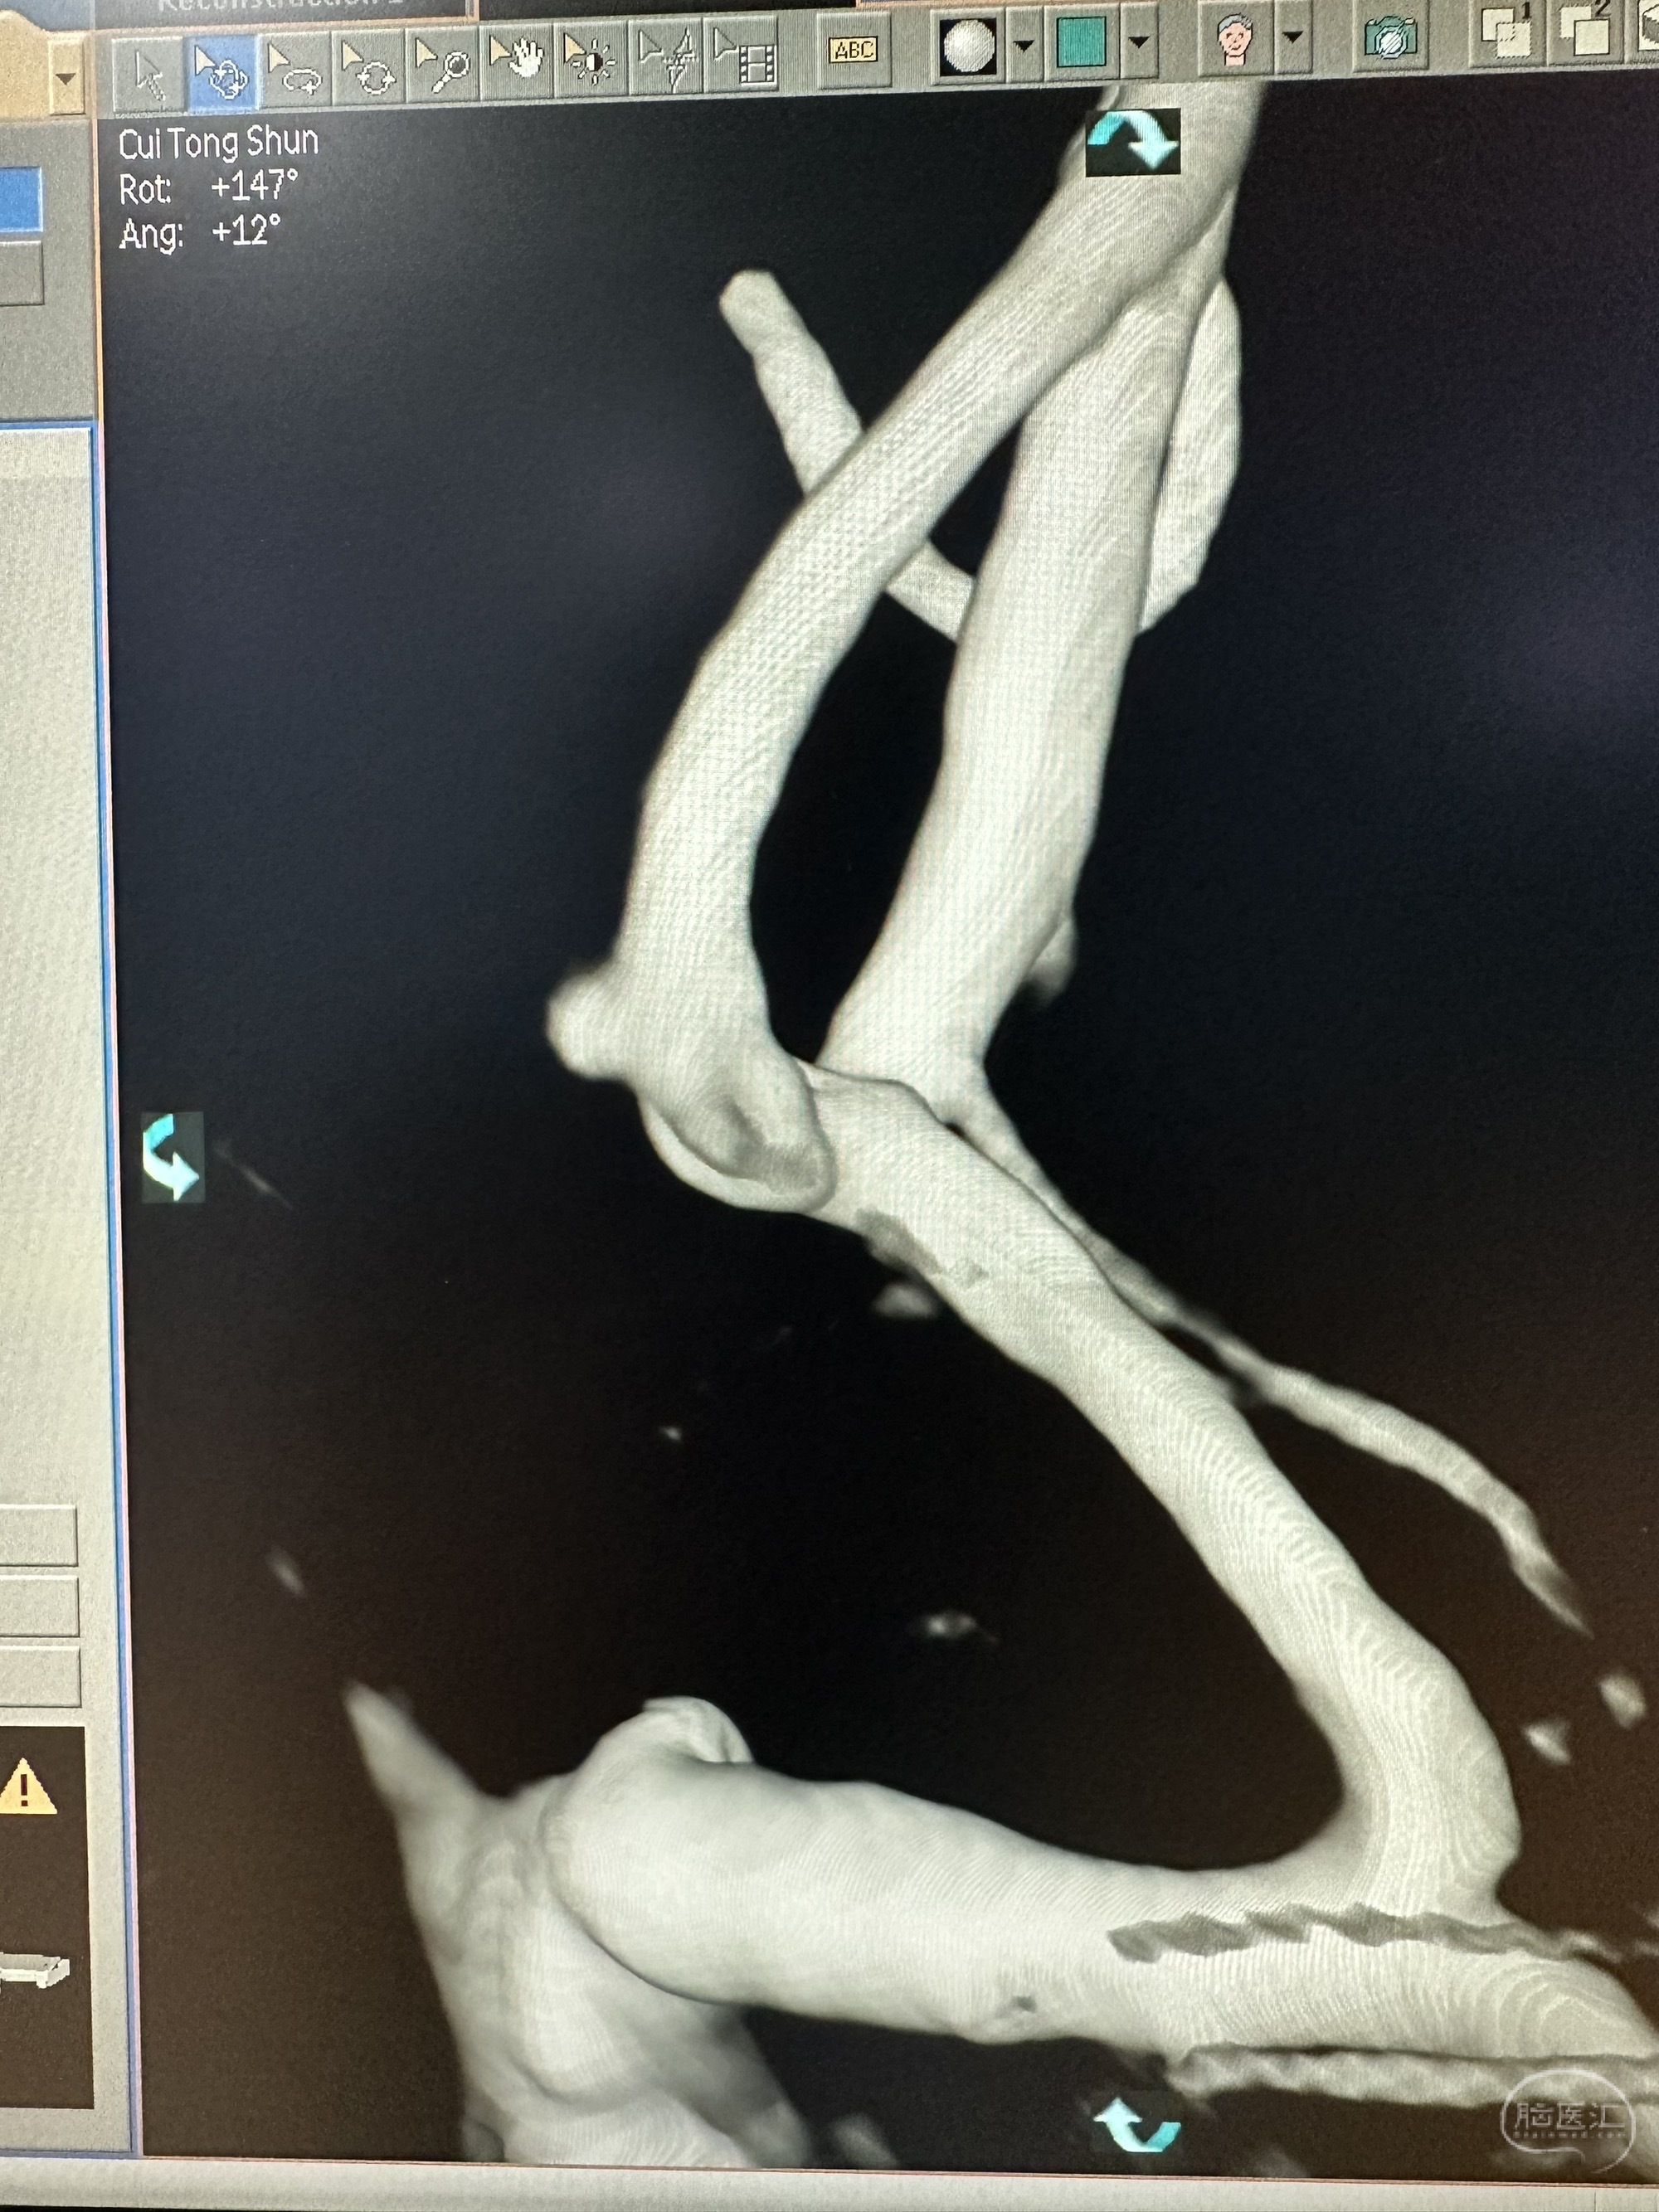

3D成像考虑前交通一个微小动脉瘤和一个A2动脉瘤,考虑前交通动脉瘤为破裂动脉瘤

另外一个角度